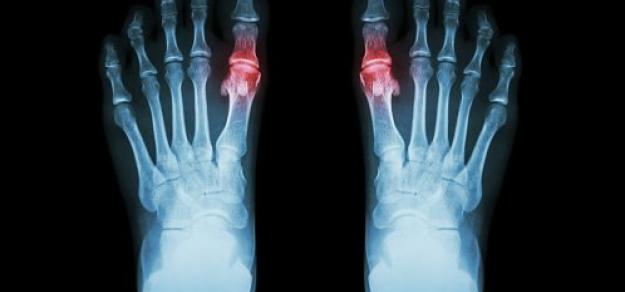

En pacientes con gota que iniciaron una terapia para reducir el urato, el riesgo de eventos cardiovasculares se redujo en aquellos a los que se les prescribió profilaxis con colchicina en comparación con aquellos a los que no se les prescribió profilaxis. Estos hallazgos proporcionan un argumento adicional para el uso de colchicina para la profilaxis de los brotes de gota.  The Lancet Rheumatology, diciembre de 2024.